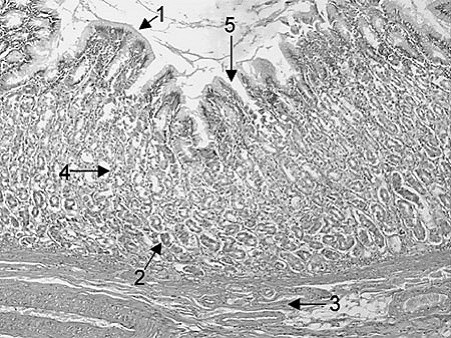

The chief or peptic (zymogenic) cells of the gastric glands secrete pepsinogen. The latter is converted to pepsin, a 35-kilodalton (kDa) proteolytic enzyme, when the pH in the stomach falls below 5.0. In Following figure, which of the following arrows point to the location of chief or peptic (zymogenic) cells?

Arrow 2 points to the base of the gastric glands where chief or peptic (zymogenic) cells tend to be clustered. Arrow 1 points to the luminal surface of the stomach where mucus-secreting cells are found.

Arrow 3 points to the muscularis mucosae. Arrow 4 points to the middle of the gastric glands where parietal or oxyntic cells tend to be most numerous. Arrow 5 point to the side of a gastric pit where mucus-secreting cells are also found.